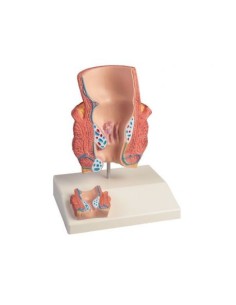

Modello per palpazione del seno, tre seni singoli su supporto - 3B Scientific L55

Modello per palpazione del seno, tre seni singoli su supporto - 3B Scientific L55